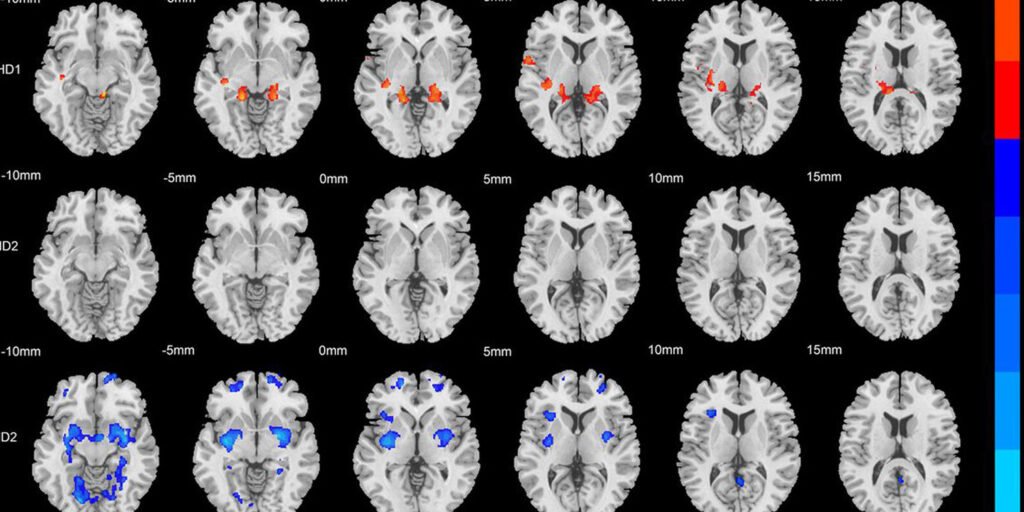

To overcome this hurdle, the team used advanced machine learning algorithms to group patients purely based on their brain anatomy. This computational tool sorts through large amounts of anatomical data to find hidden biological patterns that human observers might miss. The algorithm successfully identified two separate physical subtypes hidden within the patient group.

Once patients were classified into these two categories, distinct physical and behavioral patterns emerged. Researchers found that previously contradictory data began to make sense when viewed through the lens of these new groupings. Each subtype showed unique characteristics of brain volume changes and behavioral trends.

The first subtype was characterized by increased gray matter across several regions of the brain. Upon closer examination, the researchers found that these physical increases were concentrated in the frontal region and cerebellum. The frontal region handles higher cognitive functions such as working memory, and the cerebellum manages attention and motor coordination.

Behaviorally, patients in this first subtype suffered the most from severe inattention. The researchers noted that structural changes in this group were strongly related to an inability to maintain concentration. The physical growth of these specific brain areas appears to directly impact a patient’s attention span.

The second subtype showed almost the opposite physical reality. This group of patients showed extensive reduction or atrophy of gray matter compared to the neurotypical control group. This tissue loss was particularly pronounced in the bilateral cerebellum, frontal regions, and hippocampus.

The hippocampus is a specialized brain structure deeply involved in memory formation, spatial cognition, and internal motivation. In this second subtype, structural deterioration in these regions was associated with increased overall disease severity. These patients exhibited both symptoms of inattention and highly hyperactive or impulsive behavior.